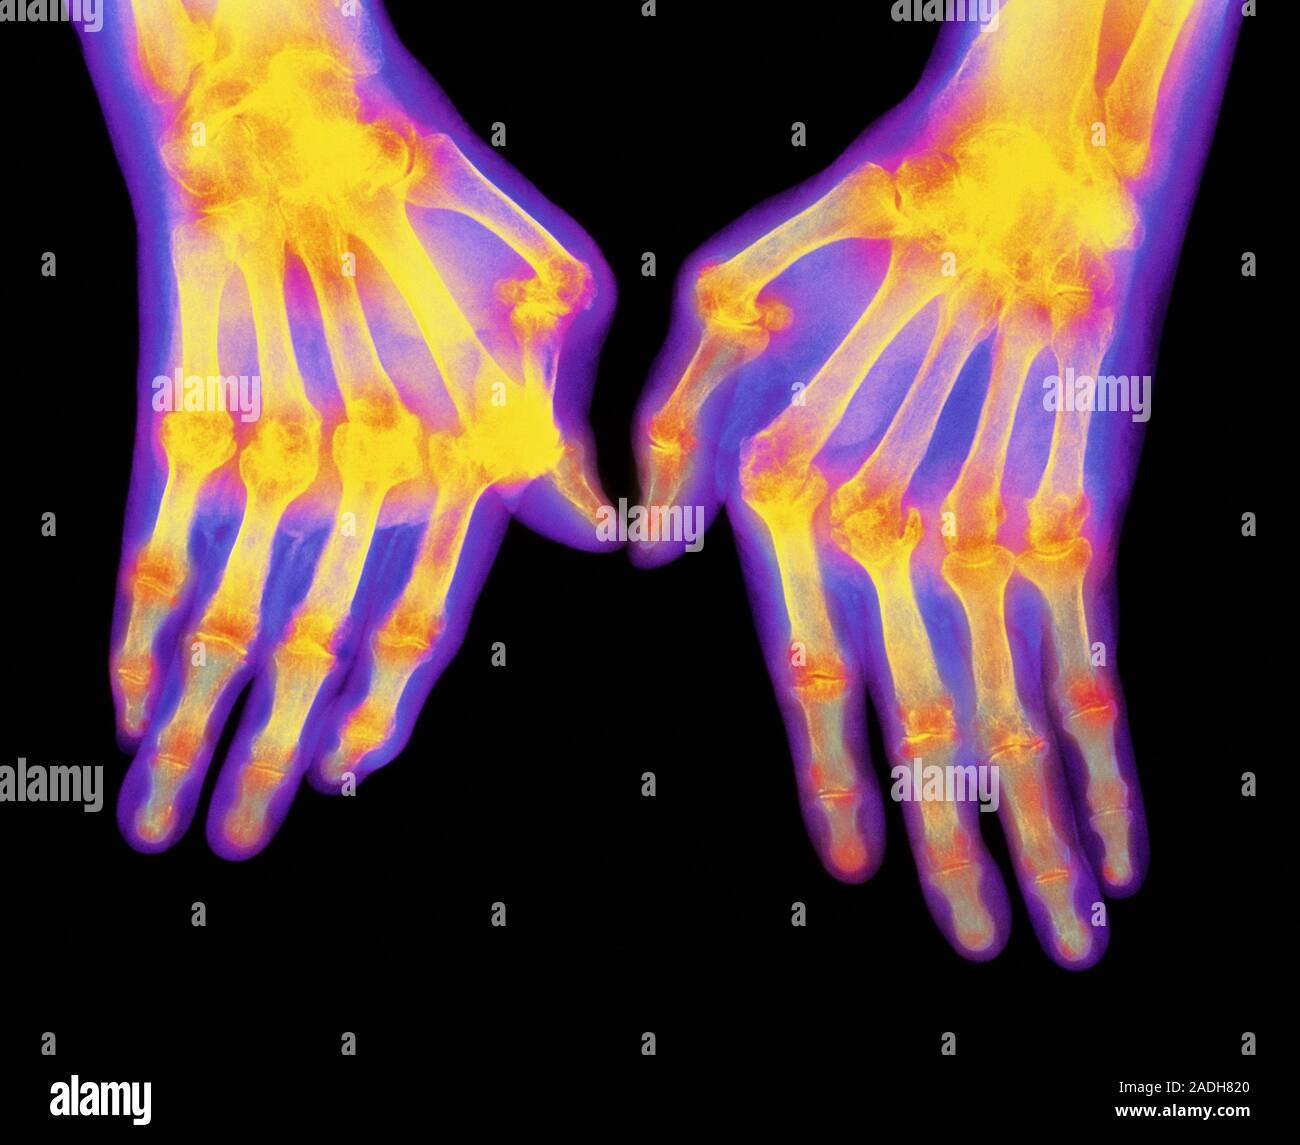

From www.alamy.com

Arthritic hands. Coloured computerenhanced Xray of hands suffering Oranges And Rheumatoid Arthritis Research shows that getting the right amount of. We aimed to summarise the current knowledge on the role of a range of beverages in the context of. if you’re concerned about how inflammatory foods for rheumatoid arthritis are affecting your symptoms, talk to your doctor about. do oranges and other citrus fruits trigger rheumatoid arthritis (ra) flares? . Oranges And Rheumatoid Arthritis.